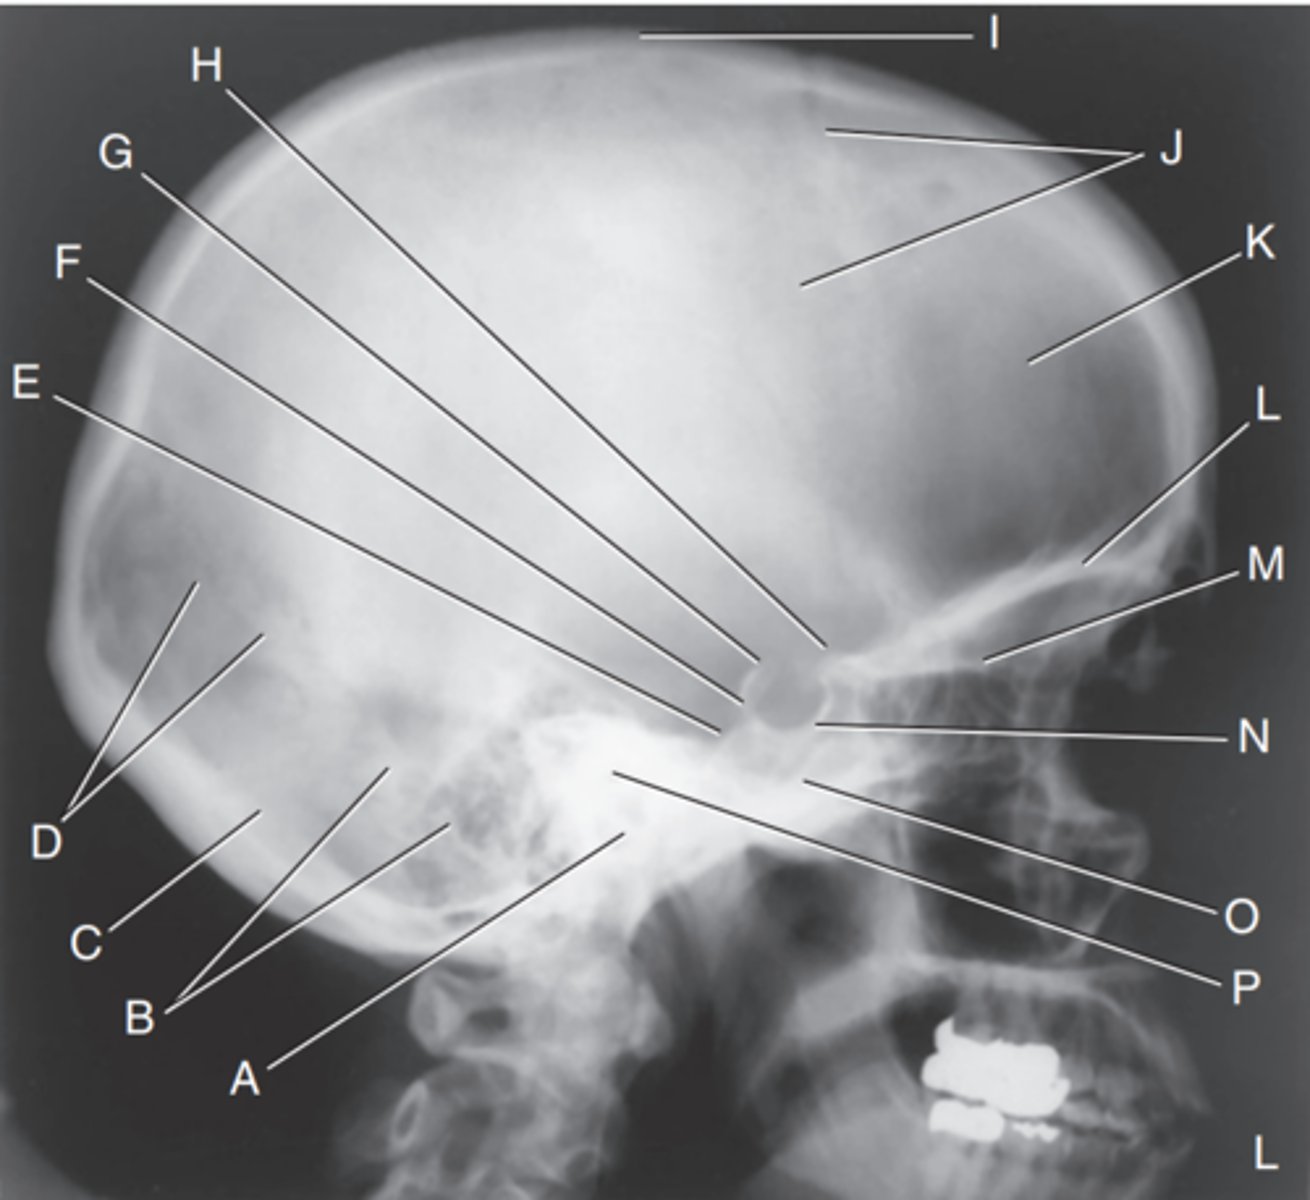

EAM

Label A

Mastoid portion of temporal bone

Label B

Occipital bone

Label C

Lambdoidal suture

Label D

Clivus

Label E

Dorsum sellae

Label F

Posterior clinoid processes

Label G

Anterior clinoid processes

Label H

Vertex of cranium

Label I

Coronal suture

Label J

Frontal bone

Label K

Orbital plates

label L

Cribriform plate

Label M

Sella turcica

Label N

Body of sphenoid (sphenoid sinus)

Label O

Petrous portion of temporal bone

Label P